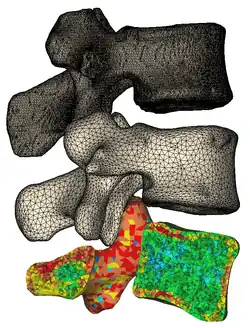

Materialise Mimics calculates surface 3D models from stacked image data such as Computed Tomography (CT), Micro CT, Magnetic Resonance Imaging (MRI), Confocal Microscopy, X-ray and Ultrasound, through image segmentation. The ROI, selected in the segmentation process is converted to a 3D surface model using an adapted marching cubes algorithm that takes the partial volume effect into account, leading to very accurate 3D models.[2][3] The 3D files are represented in the STL format.

Mask Creation

The "New Mask" tool can be used to highlight specific anatomy from the DICOM data.

-

Image segmentation

-

3D model

3D model